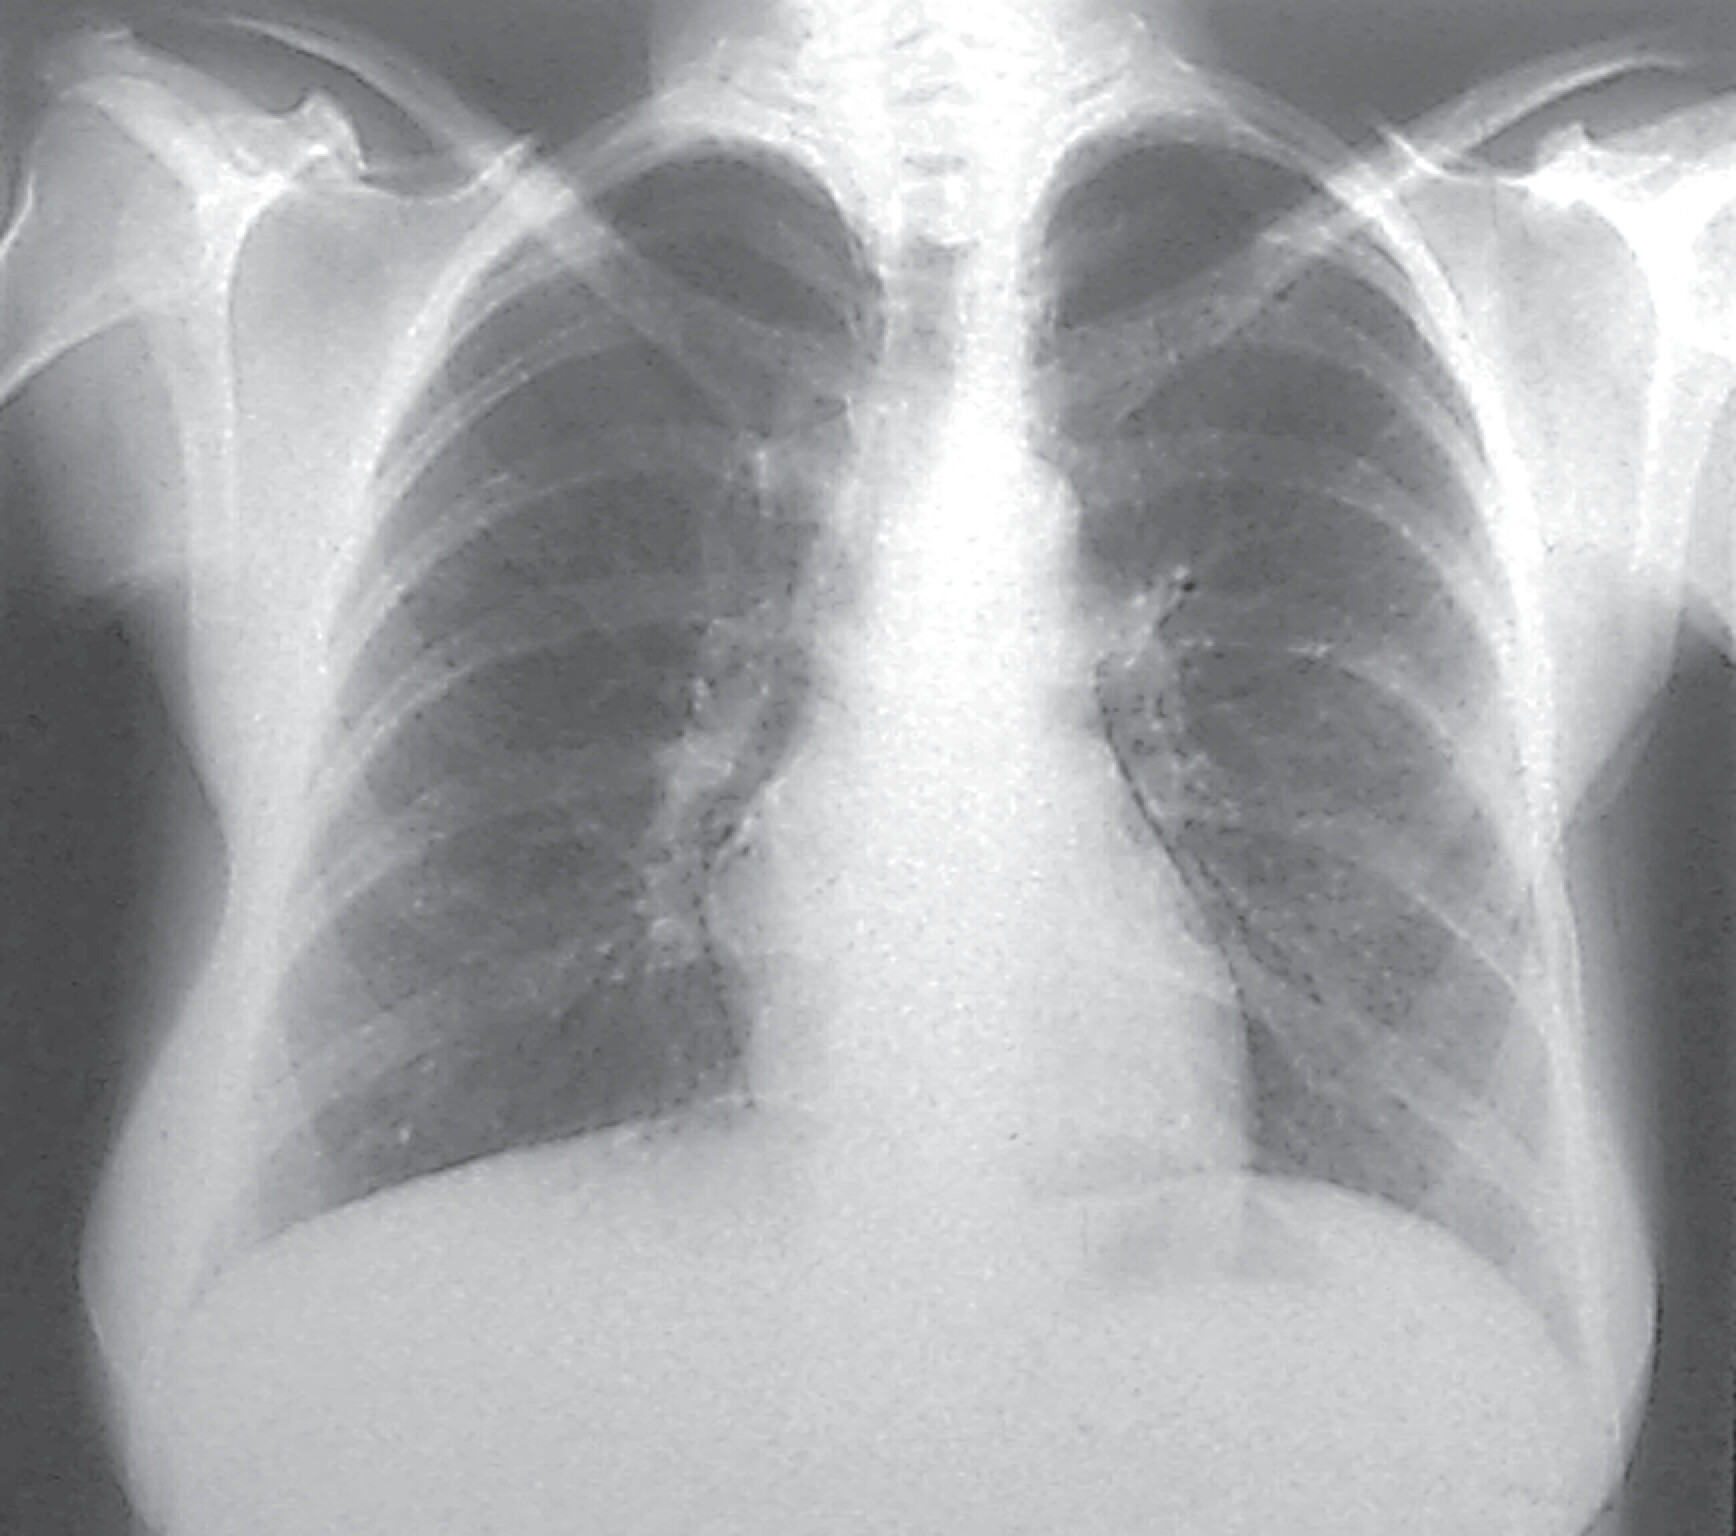

Diagnostik

Abb. 27.6 Silikose in der Röntgen-Thorax-Übersicht

Röntgen-Thorax-Übersicht p.–a.: Es kommen disseminierte, unterschiedlich große, relativ scharf begrenzte Fleckschatten in beiden Lungen zur Darstellung. Die Pleura ist abschnittsweise verbreitert.

(Quelle: Krombach G. Lunge und Pleura. In: Krombach G, Mahnken A, Hrsg. Radiologische Diagnostik Abdomen und Thorax. Stuttgart: Thieme; 2015)